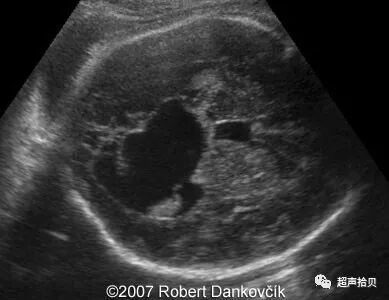

图2:冠状超声图显示位于后颅窝蛛网膜囊肿

图1,2 二维超声:孕32周:经胎儿颅骨的横切面显示第三脑室扩展,脑半球间的蛛网膜囊肿扩展至右侧

图像3,4:二维超声检查; 怀孕32周; 通过胎儿颅骨的冠状面显示扩张的侧脑室和半球囊肿向右延伸